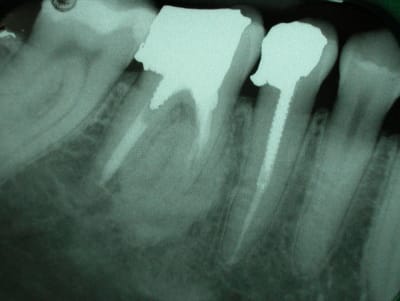

qu'est que cela peut il etre?

dent asymptomatique.

Normal mon chou, rien à faire lésion cemento-osseuse très difficile à classer même pour l'oms

tu peux écarter les fibromes cemento-ossifiant (il manque le halo radio clair périphérique) e n'est pas non plus une dysplasie fibreuse il n'y apas de déplacement de structure dentaire tu peux t'orienter vers une dysplasie céménto-osseuse péri apicale à forme dense quel age? Femme?

c'est^pas méchant, c'est souvent une formation cementoïde corrélable au traitement endo, l'os est fou et ne reconnaît plus les cellules cimentaire...

je ne suis pas endo, mais en temps qu'osseuphile je ne rettt pas pas d'inflammation sup dans ce flou ossifiant et les images en distal de la 7 c'est là depuis longtemps ou c'est de l'amalgame tout frais, fais ta couronne en expliquant la présence de cette image ostéocondensante à la patiente , femme 3 décade correspond bien avec une dysplasie cemento-osseuse terme anapath qui veut dire on s’en fout il ya des cellules cementaire et osseuses en structure malformative résultant d'une anomalie du développement d'un tissu .